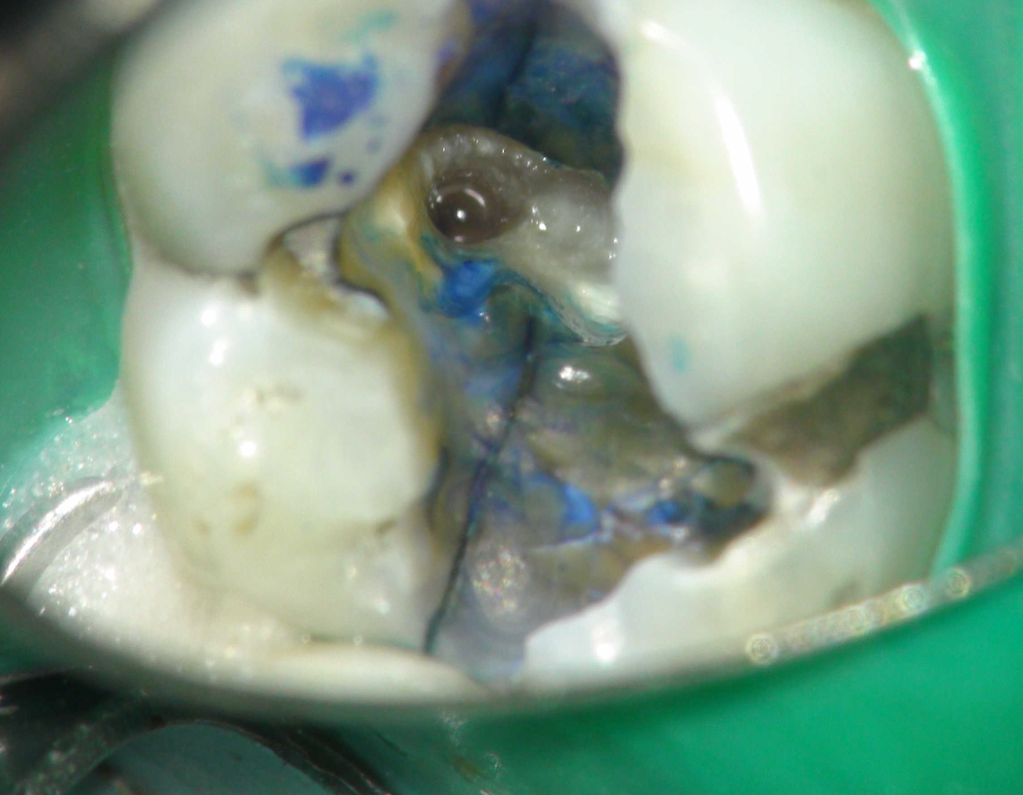

Reconstrucción preendodóntica

Reco pared vesticular

Reco preendo + 4 conductos molar superior

Reco preendo, 2o Molar superior